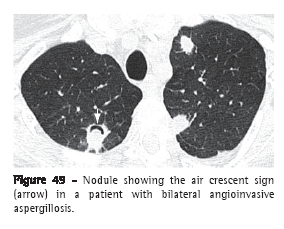

Air crescent sign (sinal do crescente aéreo)

The air crescent sign corresponds to a collection of air of variable size and in the form of a crescent or half moon, located in the periphery of a nodule or mass and presenting soft tissue density; in the proper clinical context, this finding is suggestive of angioinvasive aspergillosis in the recovery phase (Figure 49).(77-79) In this case, the air crescent sign is secondary to the retraction of infarcted pulmonary parenchyma and the resorption of necrotic tissue in the peripheral region of the lesion, causing the space between the dead tissue and the adjacent parenchyma to be filled by air.(78) This sign is also used to describe the findings of the fungus ball, in which there is a collection of air surrounding the intracavitary lesion or interposed between the upper wall of the preexisting cavity and the hanging intracavitary lesion (Figure 7).(7) The air crescent sign has also been described in other diseases, such as intracavitary hemorrhage, bacterial abscess and lung cancer.(80,81)

See also Fungus ball.